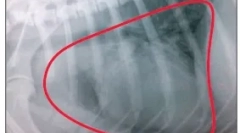

Рентгенография, ултразвуково изследване, всички кръвни изследвания и свързани анализи.